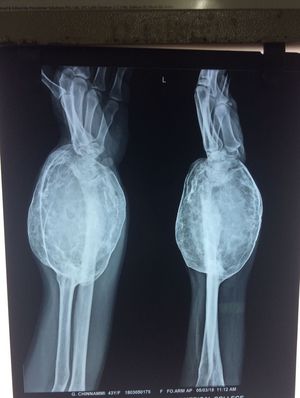

I see 43 yo, is it correct? If so, it is unlikely an osteosarcoma at that age. Maybe GCT?

Osteosarcoma..I think coz the primary lesion looks to be near the metaphysis of the bone.!?

GCT (myeloplaxe tumor) ? differential dg could be made with the aneurysmal bone cyst (more common in children)